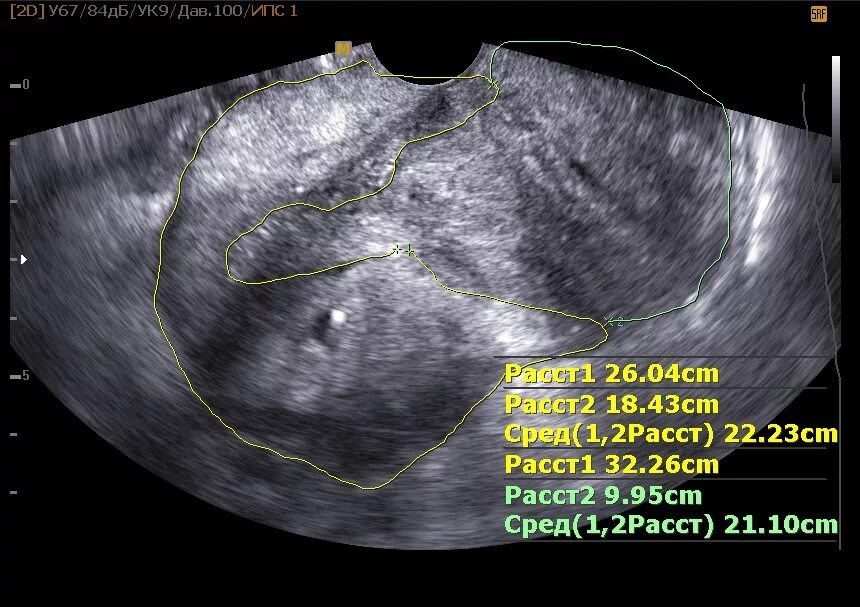

Узел в матке тип 4